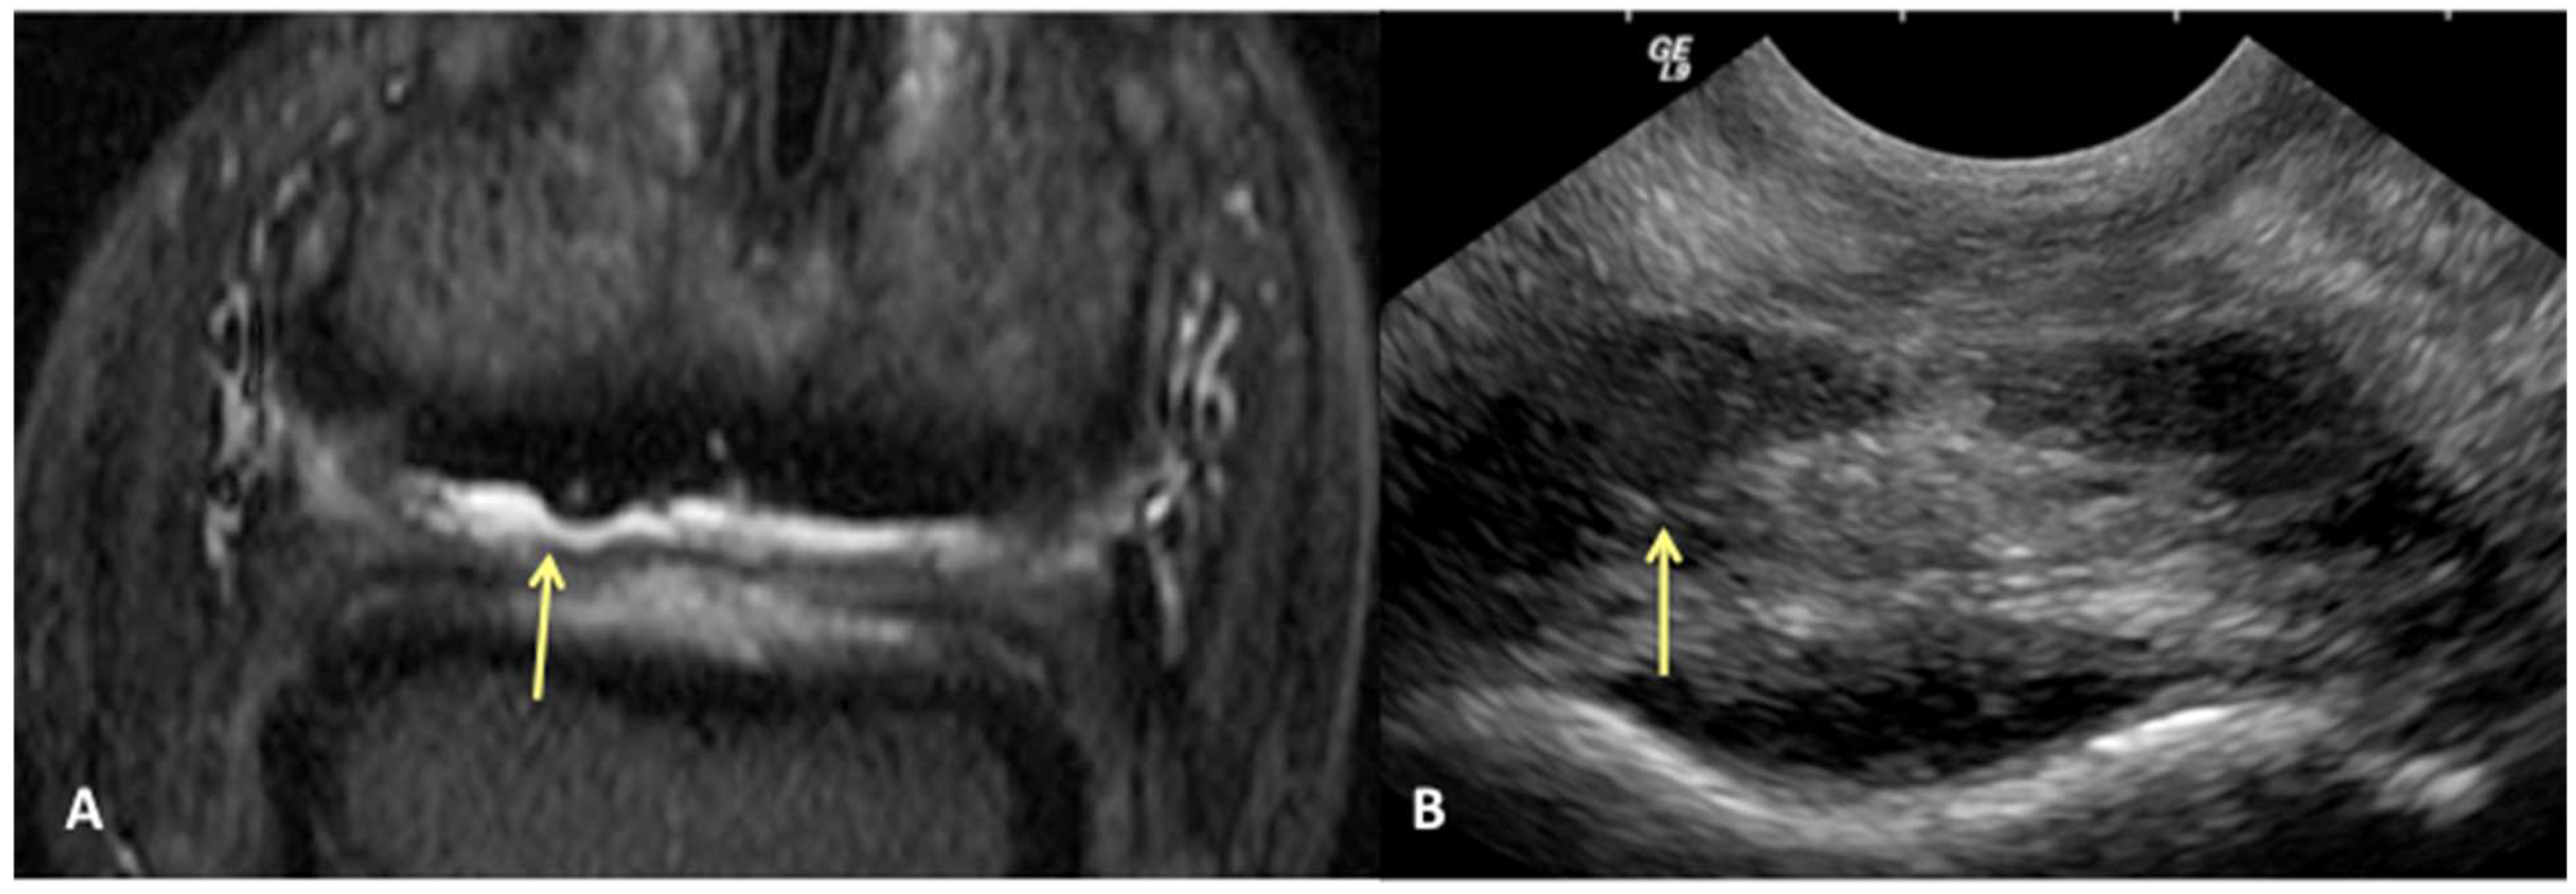

Results of sensitivity, specificity, and accuracy for comparisons of the findings of the DDFT, CSL, and navicular bursa are listed in Table 2. The low number of distal interphalangeal joint collateral ligament abnormalities resulted in low power for the statistic calculation, but prevalent findings are reported below. Ultrasound had the highest sensitivity for detecting enlargement and fiber damage of the dorsal aspect of the DDFT compared to identification of dorsal tearing of the DDFT on MRI, with a sensitivity of 85%, but it was less specific (60%) (Figure 1). Ultrasound was the least sensitive versus MRI to detect displacement (sensitivity 35%) of the CSL but was most specific for this finding (81%). Ultrasound also had a low sensitivity for detecting enlargement of the CSL (42%) but a specificity of 78% (Figure 2). Similarly, ultrasound was also less sensitive to detecting navicular bursa proliferation with a sensitivity of 47% but had higher specificity (78%) (Figure 3).

Figure 1. Transverse STIR MR image (A) and corresponding transverse US image (B), obtained at the level of the proximal recess of the navicular bursa. Palmar is on the top of the image, dorsal is on the bottom of the image, lateral is on the left. There is large area of bulging of the dorsal aspect of the lateral lobe of the deep digital flexor tendon (yellow arrows). All MR images are flipped to have the anatomy in the MR and ultrasound images in the same orientation.